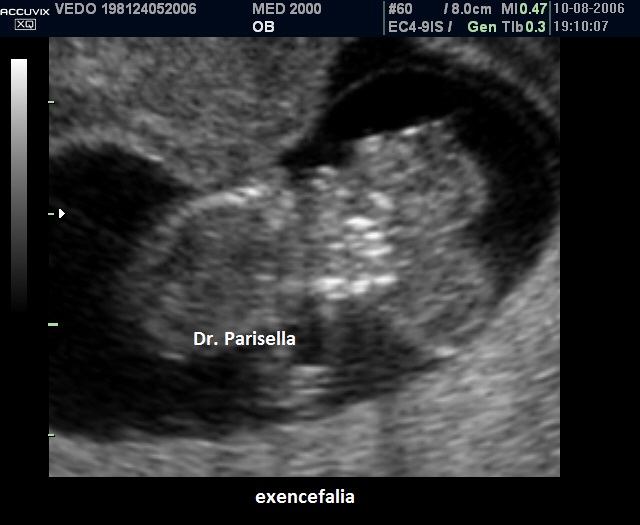

Nel I trimestre il processo distruttivo dell'encefalo non è ancora evidente per cui in questo periodo si osserva solo la mancata ossificazione delle ossa della volta cranica mentre gli emisferi cerebrali appaiono normali: si parla di acrania-exencefalia.

Alla fine del I trimestre il contatto dell'encefalo col liquido amniotico determina la distruzione del tessuto cerebrale con trasformazione dell'exencefalia in anencefalia.

La diagnosi ecografica è relativamente semplice. A 11-12 settimane la volta cranica è assente mentre gli emisferi cerebrali sono ancora riconoscibili e circondati da una sottile membrana a diretto contatto con il liquido amniotico ( acrania-exencefalia ). In sezione coronale l'estremo cefalico assume un aspetto "a mickey mouse"determinato dalla visualizzazione degli emisferi cerebrali come due strutture semicircolari al disopra delle orbite.